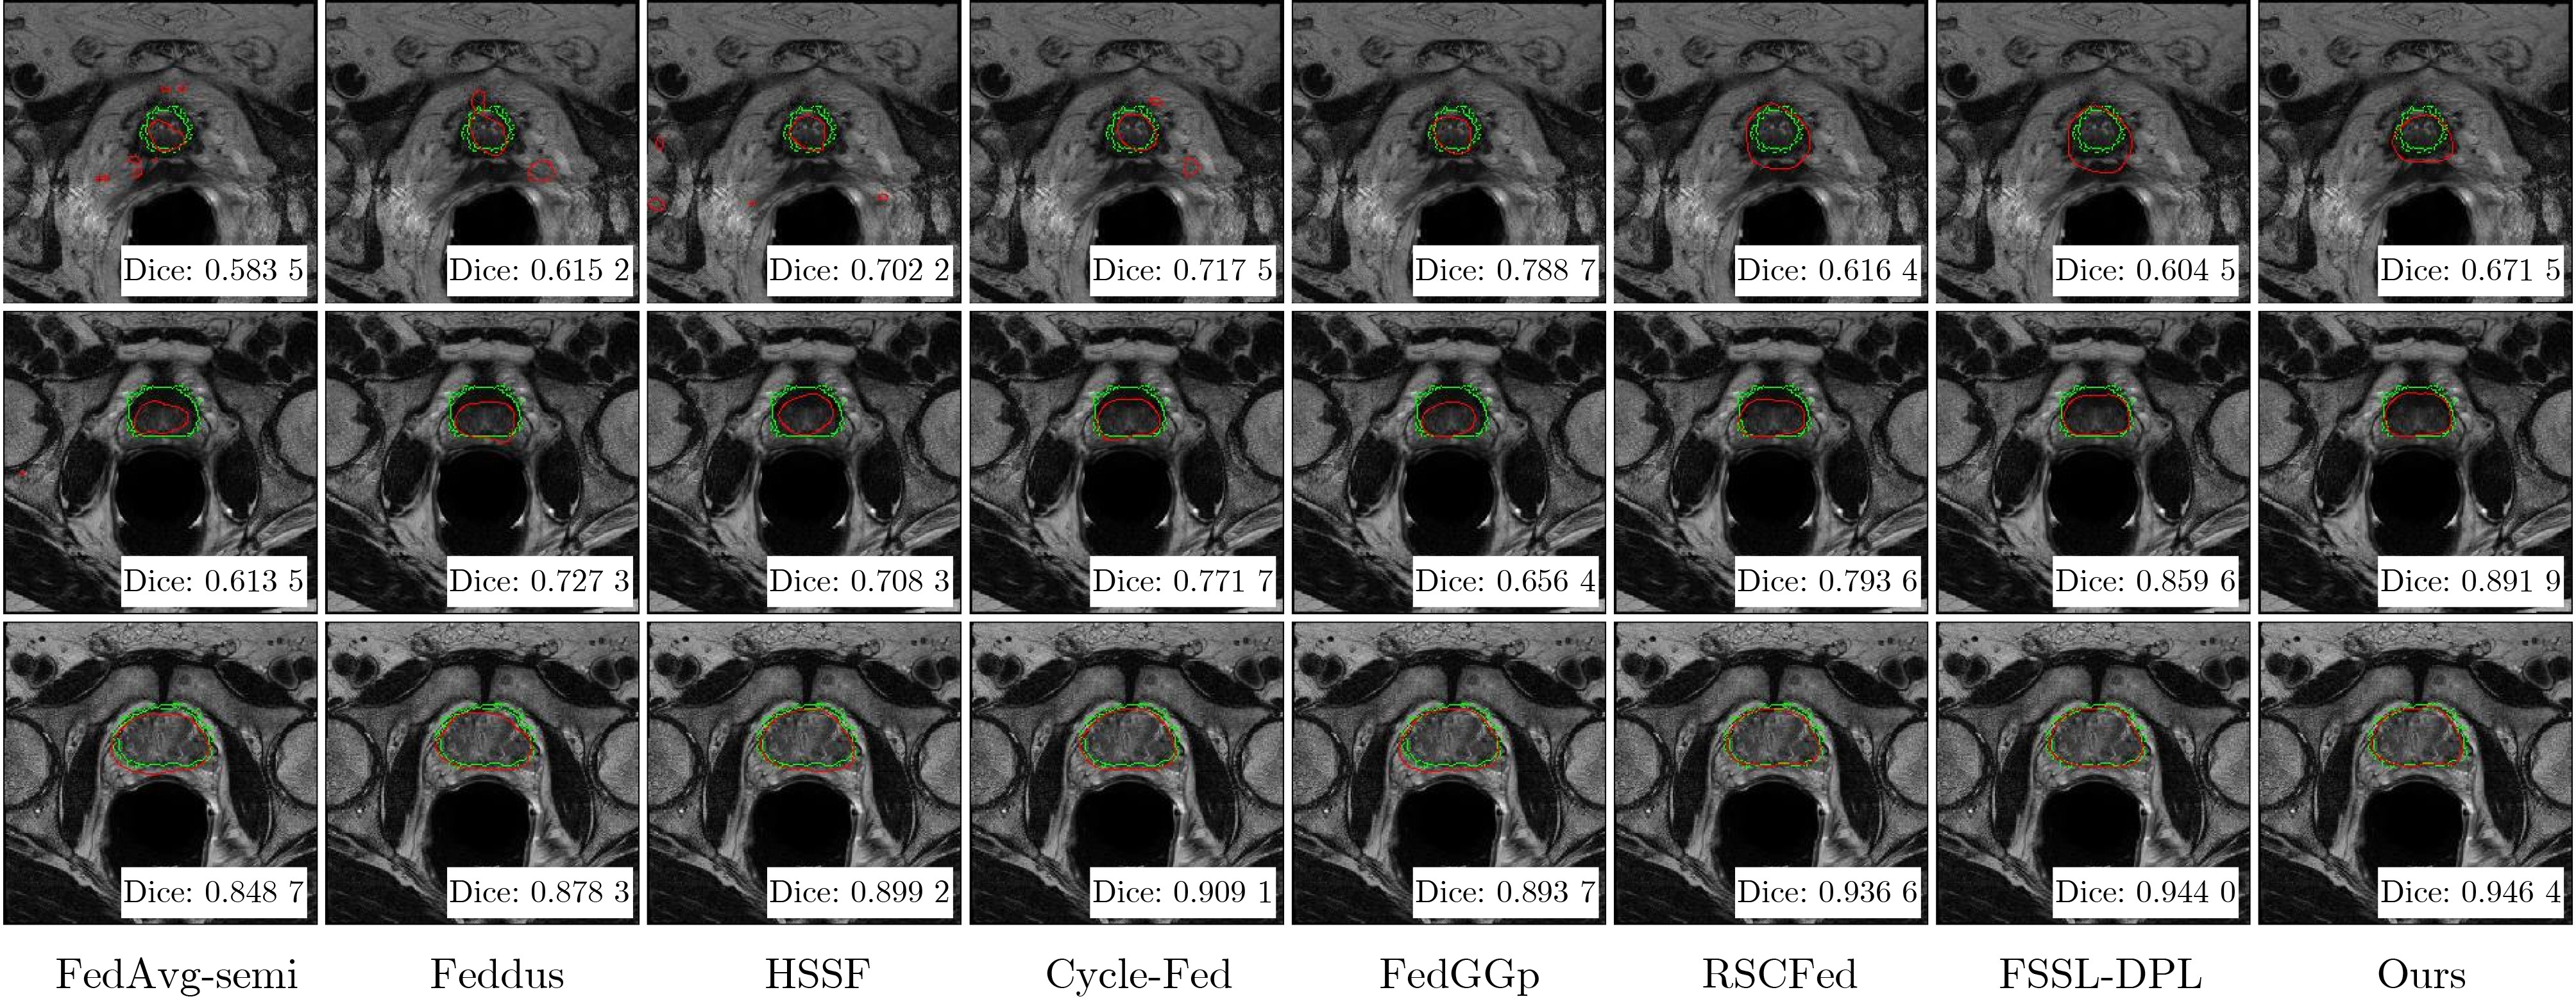

融合客户端动态筛选的联邦半监督影像分割

刘振丙, 李焕兰, 王报源, 路皓翔, 潘细朋

2026, 48(3): 960-970. doi: 10.11999/JEIT250834

摘要:

多中心协同验证是临床研究的必然趋势,但患者隐私保护、跨机构数据分布异质性以及精确标注稀缺,使传统集中式医学图像分割方法难以直接应用。为此,该文提出一种融合动态客户端管理机制的联邦半监督医学图像分割框架,利用客户端性能驱动的加权聚合和教师-学生知识蒸馏,在保护隐私的前提下充分挖掘无标签客户端价值;并设计多尺度特征融合UNet (Multi-scale Feature Fusion UNet, MFF-UNet)作为分割骨干,以增强多中心异构影像的特征表征能力,实现对前列腺区域的精准分割。基于来自6家医疗机构的T2加权前列腺MRI数据的实验表明,该方法在有标签和无标签客户端上分别获得0.8405/0.7868的Dice系数和8.04/8.67的HD95,均优于多种现有联邦半监督医学图像分割方法。